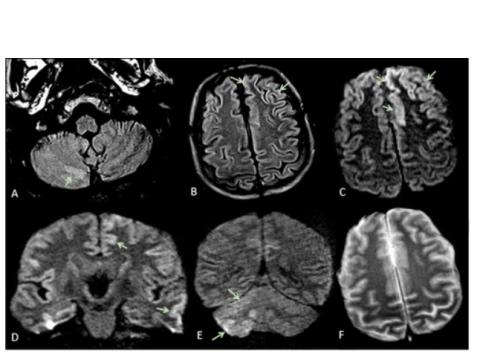

Des caractéristiques de neuroimagerie variables sont décrites chez ces patients, sans modèle spécifique mais dominées par des infarctus ischémiques aigus et des hémorragies intracrâniennes. L'étude montre que ces complications neurologiques peuvent inclure plusieurs types d’encéphalopathie dont le syndrome d'encéphalopathie réversible postérieure (avec anomalies radiologiques cérébrales bilatérales réversibles- voir visuel ci-contre), l'encéphalopathie hypoxique ischémique ou encore une exacerbation de la maladie démyélinisante. Les résultats soutiennent également une association, chez certains patients, entre COVID-19 et le syndrome de Guillain-Barré.